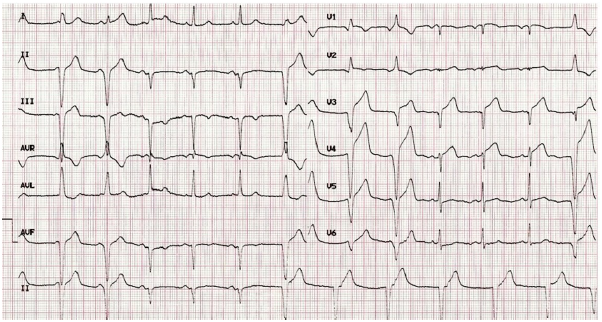

Após 60 minutos da administração do trombolítico, a paciente apresentou melhora da dor e redução significativa do supradesnível do segmento ST. Ela estava bem, mas referiu mal-estar, sendo repetido o eletrocardiograma, reproduzido abaixo.

Nesse caso, a alteração encontrada